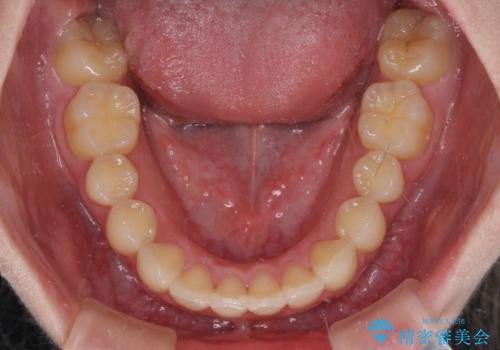

- 口元の突出感を気にして来院された患者様です。

左右ともに上顎奥歯が外を向き、下顎奥歯が内側に倒れているシザーズバイトであったため、補助装置により改善することとしました。

上下の咬み合わせは、下顎に対して上顎が相対的に前方にあったため、奥歯のシザーズバイト改善後に上顎左右第一小臼歯2本を抜歯し、上顎前突を改善していくこととしました。